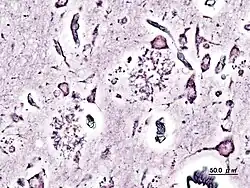

Biopsie cérébrale d'un patient atteint de maladie d'Alzheimer.

La pratique de la neuropathologie moderne repose essentiellement sur l'examen au microscope de spécimens de tissus nerveux prélevés chirurgicalement chez un patient : il peut s'agir de biopsies cérébrales ou de lésions médullaires détectées par les techniques d'imagerie médicale. Il peut aussi s'agir de biopsies de nerfs périphériques ou de biopsies musculaires. Plus rarement qu'au XIXe siècle, la neuropathologie peut encore avoir recours à l'autopsie pour établir un diagnostic post-mortem.

Les échantillons prélevés sont fixés et inclus dans des blocs de paraffine, puis coupés en fines lamelles au microtome.On utilise largement en première intention les colorations simples comme celles à l'hématoxyline-éosine (HE). Lorsqu'un diagnostic rapide est nécessaire, par exemple au cours d'une intervention chirurgicale sur une tumeur (diagnostic extemporané), les fragments prélevés par le neurochirurgien sont congelés et découpés à l'aide d'un cryotome. On a largement recours aux techniques d'immunofluorescence directe qui utilisent des anticorps dirigés contre différents antigènes tumoraux.